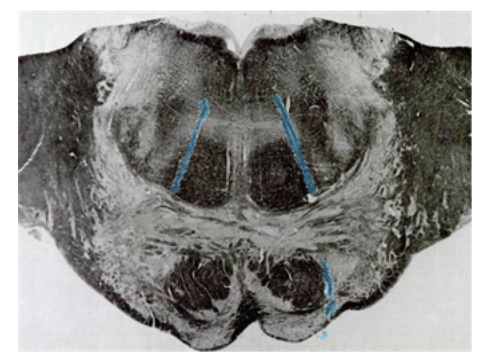

What does the caudal pons (at CN VI) cross section kind of resemble?

What level cut of the brainstem is this?

What does the cross section of caudal pons (CN VII) look like?

What cross section is this? What does it kind of look like?